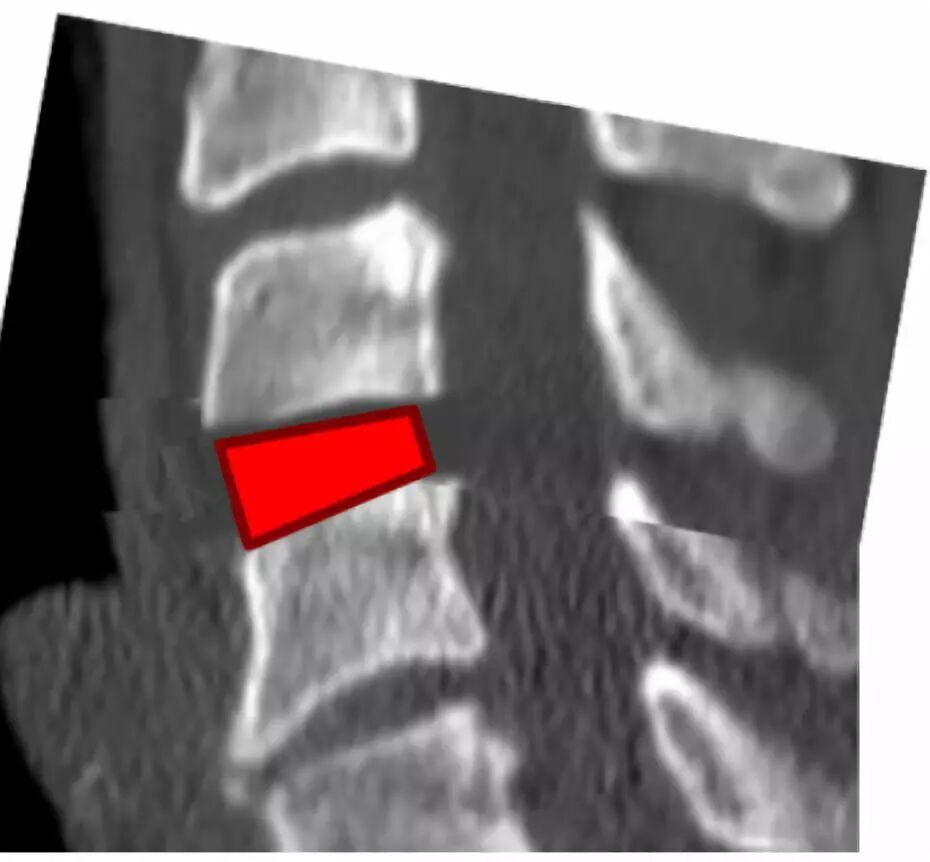

去除前部和后部骨赘(头侧和尾侧)以形成用于插入椎间融合器的平行通道。

用刮匙和/或锉刀进行终板准备以增强椎间融合。

前板需选择适当的尺寸,避免过长延伸影响到相邻的椎间盘空间。

矢状面上将螺钉置于“发散”状态以使压力传递到椎间植入物上。

轴位平面上将螺钉内聚(“三角”)放置以防止拉出。